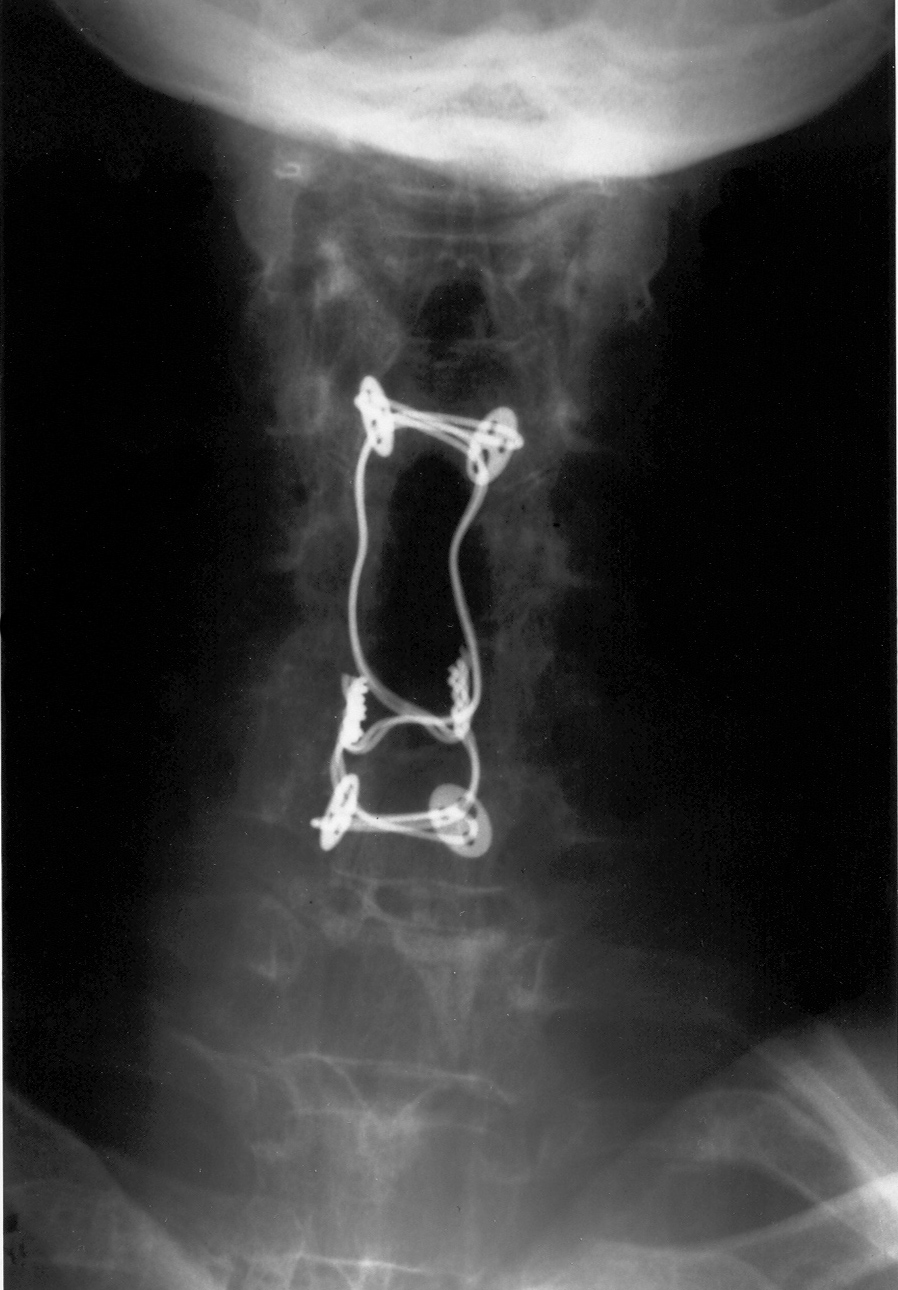

44 year-old man with C7 vertebral fracture. Posterior figure of 8 wire fixation extends from C4 to C7 |